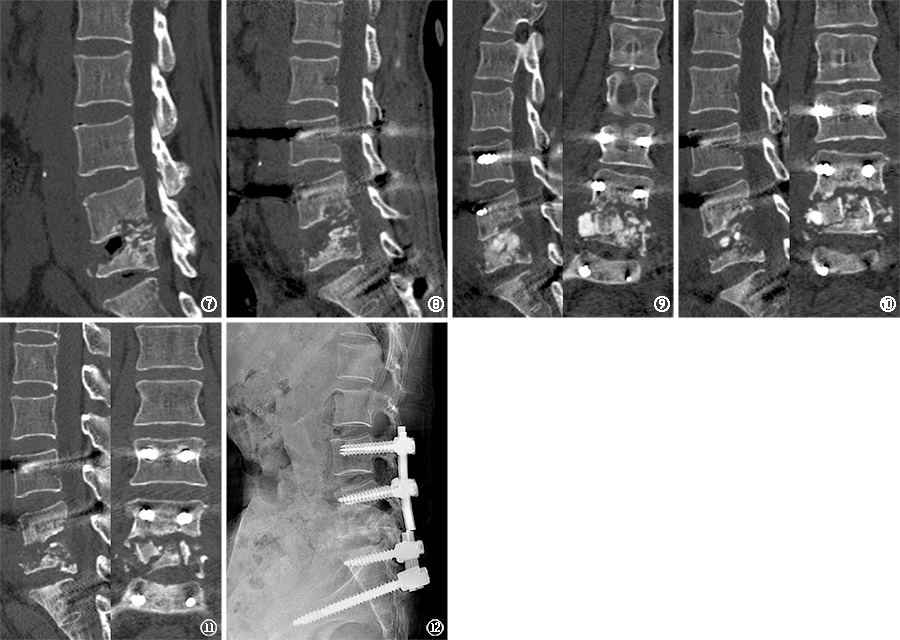

图7~12 病例2,患者,女,62岁。图7 2021年4月21日,入院腰椎CT扫描矢状位重建,提示第4、5腰椎及第1骶椎骨质破坏、边缘硬化,第5腰椎病理性压缩性骨折,局部后突 图8 2021年5月12日行椎弓根钉内固定术后,5月13日复查CT提示第5腰椎局部后突矫正 图9 2021年7月2日复查腰椎CT显示第4、5腰椎椎体内高密度植骨影 图10 2021年8月10日复查腰椎CT,提示植骨未见融合 图11 2021年11月19日复查腰椎CT,提示第5腰椎椎体进一步坍塌,第4、5腰椎骨质破坏进一步加重 图12 2021年12月7日复查腰椎X线片,提示第5腰椎椎体继续塌陷病例2,患者,女,62岁。